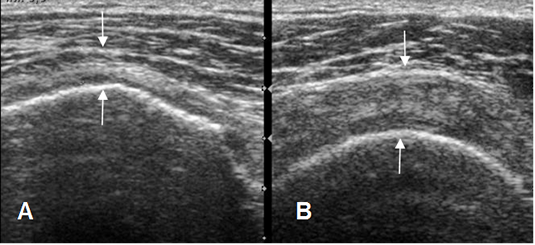

Fig 120. Ruptura parcial del supraespinoso.

Ecografía coronal. Adelgazamiento del tendón supraespinoso en A, por ruptura parcial.

Tendón normal, en el lado contralateral, foto B.